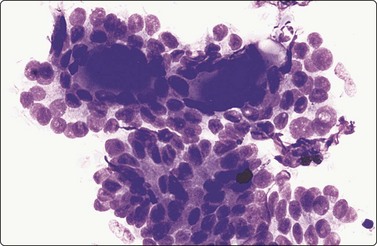

Follicular neoplasms (Figs 6.18-6.24)23,29,68,117-120

image image

Fig. 6.18 Follicular neoplasm

Cellular smears of single cells, microfollicles or rosettes in a repetitive manner; benign adenoma by histology (A, MGG, HP; B, Pap, HP).

Fig. 6.19 Follicular neoplasm

Smears very similar to Figure 6.18; follicular carcinoma with vascular invasion by histology (A, MGG, HP; B, Pap, HP).

Diagnostic criteria

Moderate to high cellularity,

Bloody, usually colloid-free background,

Prominent microfollicular pattern,

Rosettes, syncytial groups and equal-sized cell clusters,

Nuclear crowding and overlapping,

Positive immunostaining for thyroglobulin and TTF-1.

FNs are classified as benign (FA) and malignant (FC). FAs and most FCs are encapsulated tumors, occurring in one of the lobes. Histological diagnosis of a well-differentiated FC requires demonstration of capsular and/or vascular permeation. Most FNs, especially adenomas, have a uniform internal structure that is reflected in the cytological smears. FAs are more common in women and microscopically show a variety of histological patterns such as microfollicular (fetal), normofollicular, macrofollicular, trabecular, solid (embryonal), Hurthle cell and atypical adenomas.42 Cytologically, follicular lesions include FA, FC, cellular NG and FV-PC.121

Smears in FN are cellular in a bloody background that is usually devoid of colloid. Many uniform-sized follicular cell clusters, microfollicles and rosette formations are present. Syncytial aggregates, nuclear crowding and overlapping are also often seen.

The repetitive smear pattern with uniform cell population is in contrast to the variable pattern of different cell types seen in colloid and hyperplastic nodules. Microacinar clusters with a central lumen (that may contain a drop of colloid) represent microfollicles (Figs 6.18, 6.19 and 6.21B). These are characteristic of FN but may be found focally in NG. Rosette-like groupings without a lumen (Fig. 6.20) suggest a more solid growth pattern. A trabecular pattern is represented by rows and elongated aggregates of epithelial cells that resemble papillary structures when they adhere to strands of vascular stroma (see Fig. 6.33B,C). Small blood vessels with adherent epithelial cells can be found in any type of follicular neoplasm (see Fig. 6.25A).